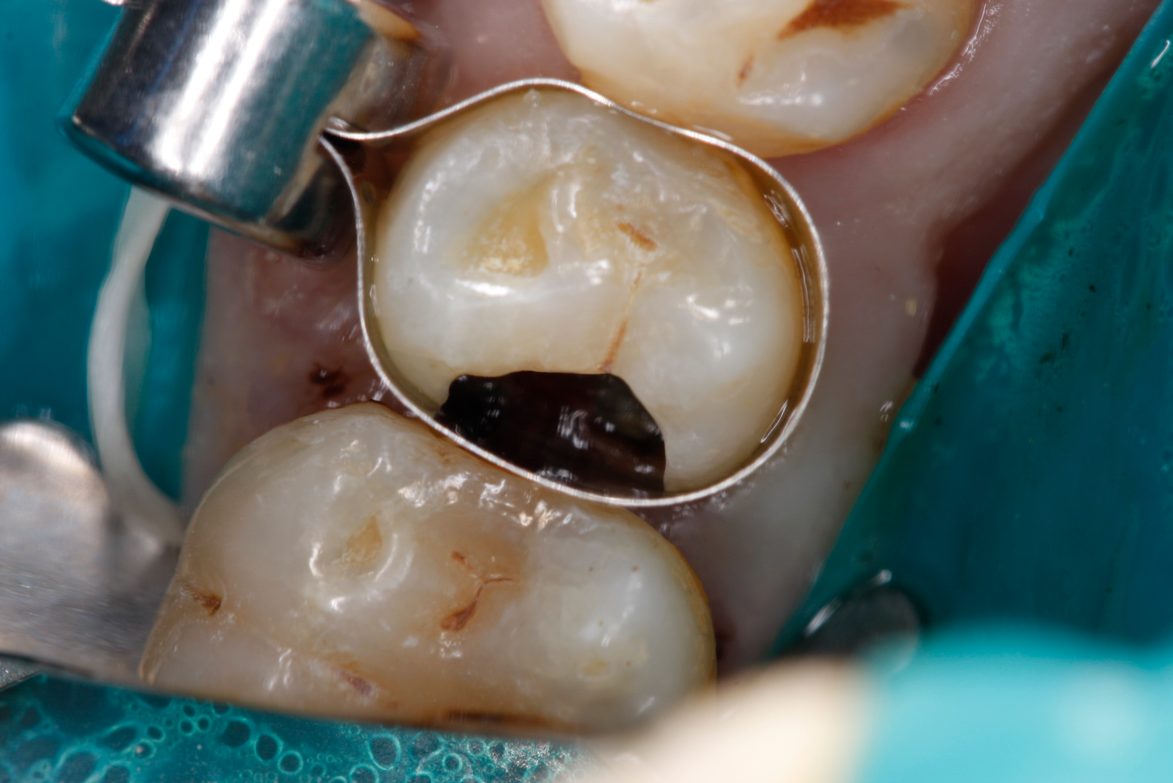

Figure 8A is a radiograph revealing deep root caries previously restored temporarily by a resident at the AEGD Residency Program clinic with glass ionomer utilizing a lateral rather than occlusal approach. After the glass ionomer failed to adhere, another resident again attempted a lateral approach that resulted in the restoration shown in Figure 8B. A third resident had success with an occlusal approach, removing a failed occlusal composite to access the distal  (Figure 9). This attempt was successful both in the preparation of the lesion and in the placement of a dual- cure bulk-fill flowable (Bulk EZ Plus, Zest Dental Solutions; alternatively: HyperFIL®, Parkell; Fill-Up!, Coltene) extruded through a bendable needle (Figure 10). Figure 11 shows the final preparation after tissue removal was accomplished with rotary gingitage; note that this was performed with the rubber dam in place. An air abrasion device (Groman Etchmaster, Groman Dental; alternatively: PrepStart H2O, Zest Dental Solutions; Bioclear Blaster, Bioclear) was used with potassium bicarbonate to remove biofilm prior to acid etching (Figure 12). Phosphoric acid 37% was utilized in a total etch fashion (Fig- ure 13 and Figure 14) for 20 seconds. Figure 15 shows the universal bond (Scotchbond Universal, 3M; alternatively: All-Bond Universal®, BISCO; Prelude One, Danville Materials) with metha- cryloyloxydecyl dihydrogen phosphate (MDP) being scrubbed into the cavity for 20 seconds. After air thinning for 20 seconds, the adhesive was light cured for 40 seconds at 1,200 mw/cm2power density (Figure 16).

Fig 9. View of existing occlusal composite to be removed to access the distal lesion on tooth No. 2.

Figure 9

Fig 10. Occlusal approach was successful in the placement of a dual-cured bulk-fill flowable. Note the depth of box form.

Figure 10